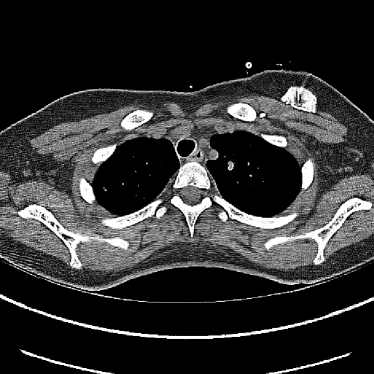

Refer to caption

(a) Clinical Standard Hybrid IR

(b) JENG

Figure 15: An example cross-plane image from the same thoracic dataset as in Fig. 14. (a) A coronal-view image slice of the clinical standard hybrid IR in soft tissue window. (b) JENG at a comparable resolution but with reduced image noise and artifacts.